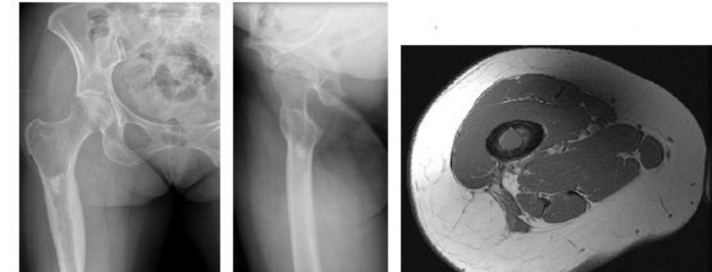

A 15-year-old male presents with deep knee pain awakening him at night. Radiographs show a permeative destructive lesion in the distal femoral metaphysis with a 'sunburst' periosteal reaction and Codman's triangle.

Biopsy confirms high-grade conventional osteosarcoma. What is the most critical prognostic factor for long-term overall survival in this patient?

Explanation

For localized high-grade osteosarcoma, the most important prognostic indicator is the histologic response to neoadjuvant chemotherapy. This is evaluated during the definitive resection. A 'good response' is typically defined as greater than 90% or 99% tumor necrosis. Patients who achieve this level of necrosis have a significantly improved disease-free and overall survival rate compared to 'poor responders' who have extensive viable tumor cells remaining.